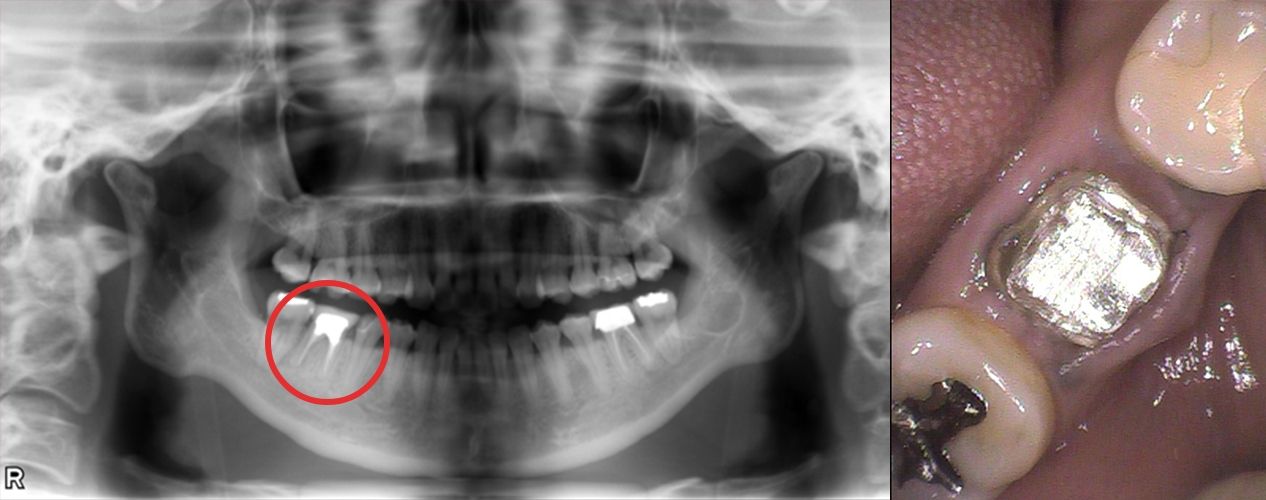

痛みと治療を繰り返す歯にお困りの方

前の医院で右下の奥歯を治療してもらっていたけれど、それでもずっと歯が痛くて…。川越歯科医院を紹介されて来院しました。

治療概要

| ご希望 | 前の医院の治療がうまくいかず、歯の痛みを治す方法を知りたい。 |

|---|---|

| 治療内容 | むし歯治療をした歯の根元に穴が開いており、膿が発生。歯を残しても再発の可能性があるため、抜歯し、インプラント治療へ。 |

| 治療期間・回数 | 約6ヶ月・6〜8回 |

| 費用 | 41万円 〜 45万円 |

| 想定されるリスクと副作用 | インプラントとGBR(歯槽骨を再生する治療)を同時に行うと痛みが1~2週間続く、腫れ、内出血 |

埋入二年後

手術を終えて

お口全体を診て、私の歯を長く残すための方法を考えていただけました。

先生から一言

ブリッジという方法もありましたが、隣り合う天然歯が綺麗な状態だったのでできるだけ周りの歯も綺麗に残せる方法をと思い、インプラントをご提案しました。結果、他の歯に影響を与えることなく、術後経過も順調です。